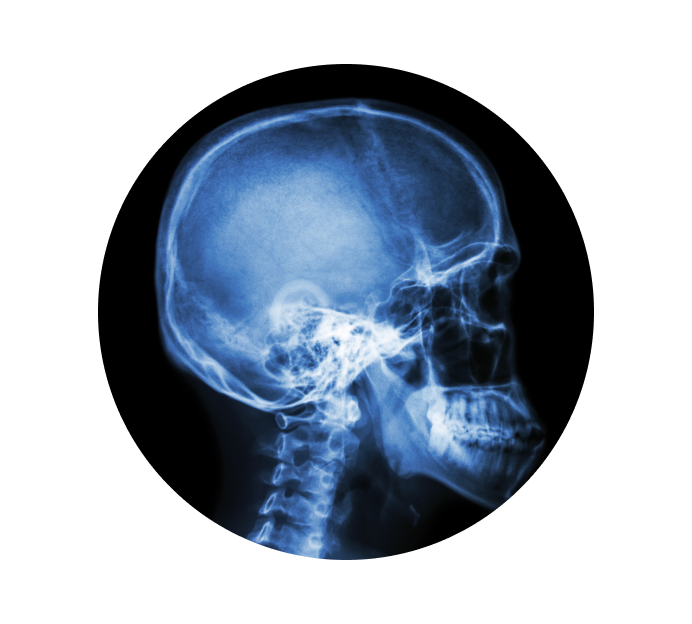

Рентген турецкого седла в Краснодаре

Турецкое седло — это костное образование, которое находится в середине черепной коробки и защищает гипофиз (железа, вырабатывающая гормоны, участвующие в процессах обмена веществ, роста и развития человеческого организма). Рентген турецкого седла делается по назначению врача для того, чтобы определить присутствие патологий. Снимок может показать форму, структуру и размеры седла, что позволит доктору определить присутствие возможных заболеваний.